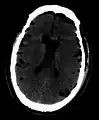

Additional images

Pneumocephaly